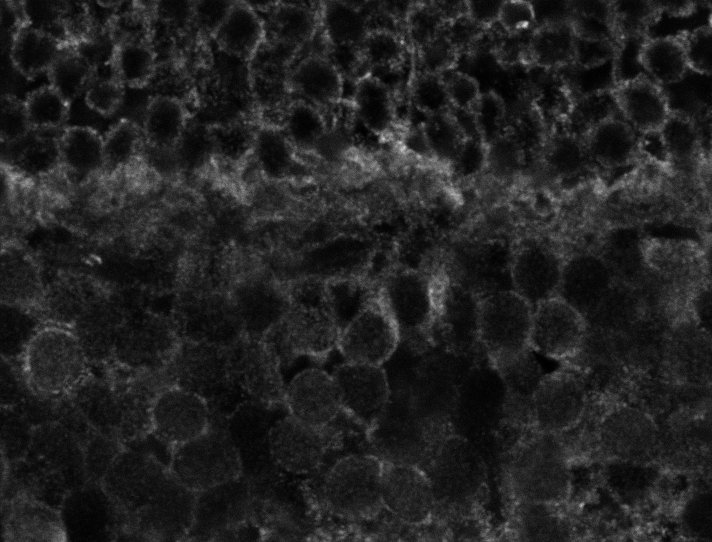

Healthy Choroid

Unhealthy Choroid